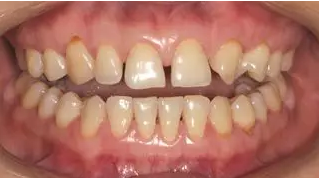

術前微笑照

術前全牙弓咬合照

術前全牙弓非咬合照

術前上前牙正面照

口腔衛(wèi)生尚可,牙齦正常。11,12,21,23 牙體完整,散在間隙,13、24、33、34 頸部楔形缺損,探診無明顯不適,叩(-),無明顯松動。冷熱刺激無明顯不適。22 缺失。上下牙咬合穩(wěn)定,覆 覆蓋正常。